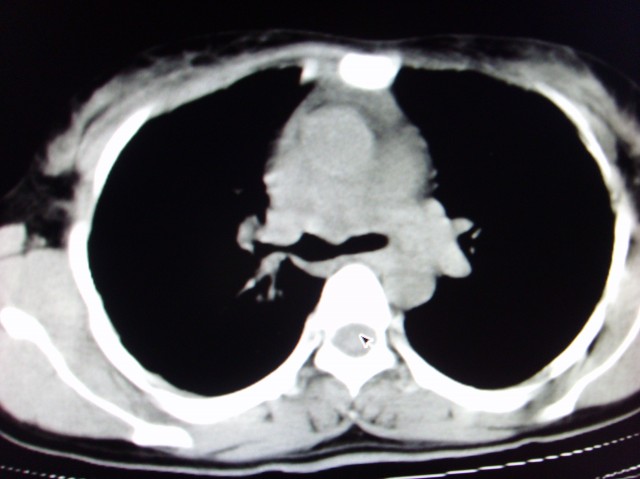

标题: CT7125:中央性肺Ca.

典型 中央型ca伴双肺、淋巴结转移

右下中心型肺癌伴双肺转移、纵隔淋巴结转移,癌性淋巴管炎可能性大

支持楼主的中央型肺癌,肺内,纵隔内淋巴结转移

支持楼主诊断:中央型肺癌,肺内,纵隔内淋巴结转移。

典型--右下中心型肺癌伴双肺转移、纵隔淋巴结转移,癌性淋巴管炎可能性大

经典病历,肿块。肺内转移、淋巴结转移。胸膜仗义

典型的中央型ca,肿快和肺门分界不清,肿快边界模糊,呈毛刺状。伴淋巴结转移。